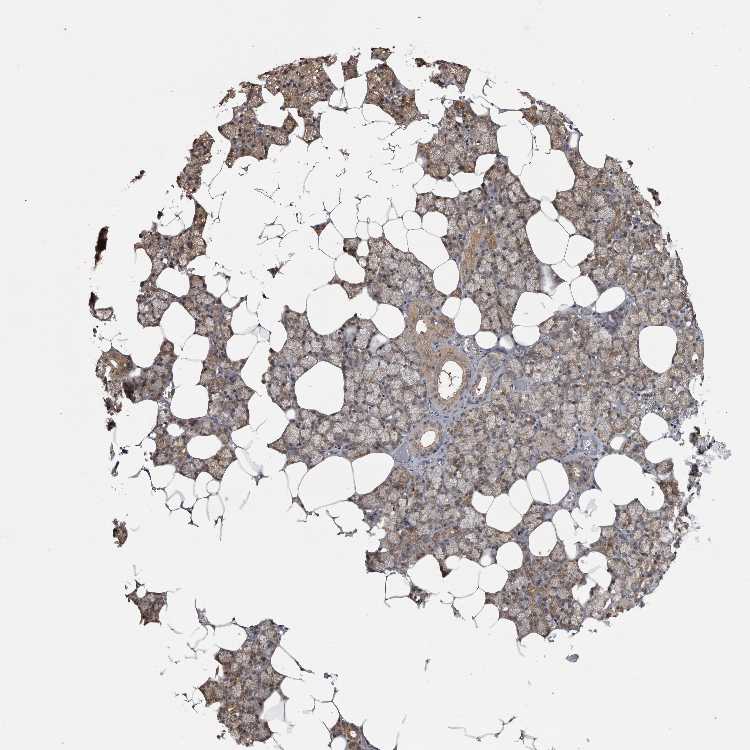

Antibody HPA026681

Glandular cells Medium